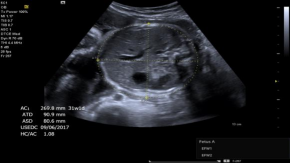

syngo®Auto OB 自动产科测量: AUTO OB 自动产科测量软件,准确识别图像边界,自动获取双顶径、枕额径、头腹围、股骨长等常用径线数据,降低测量差异性的同时提高了医生的工作效率。